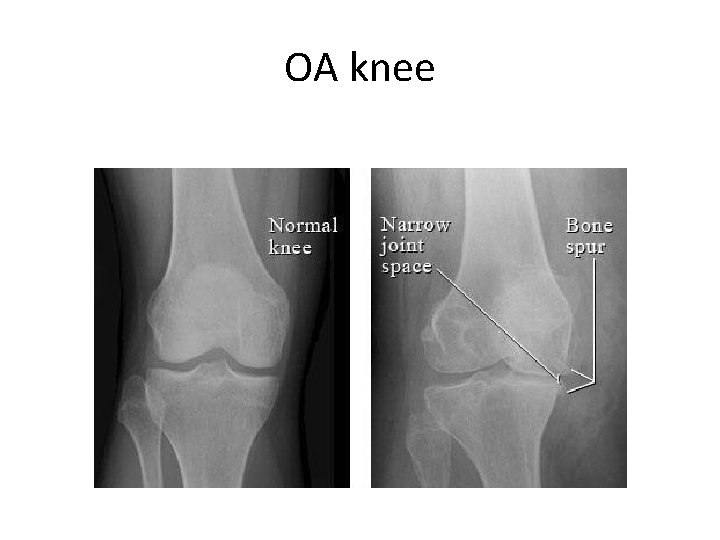

Knee • • OA Trauma – soft tissue Degenerative meniscal Patella-femoral

OA knee

Management • • • Physiotherapy – lifestyle Weight loss Exercise – therapies Injections If all fails - surgery